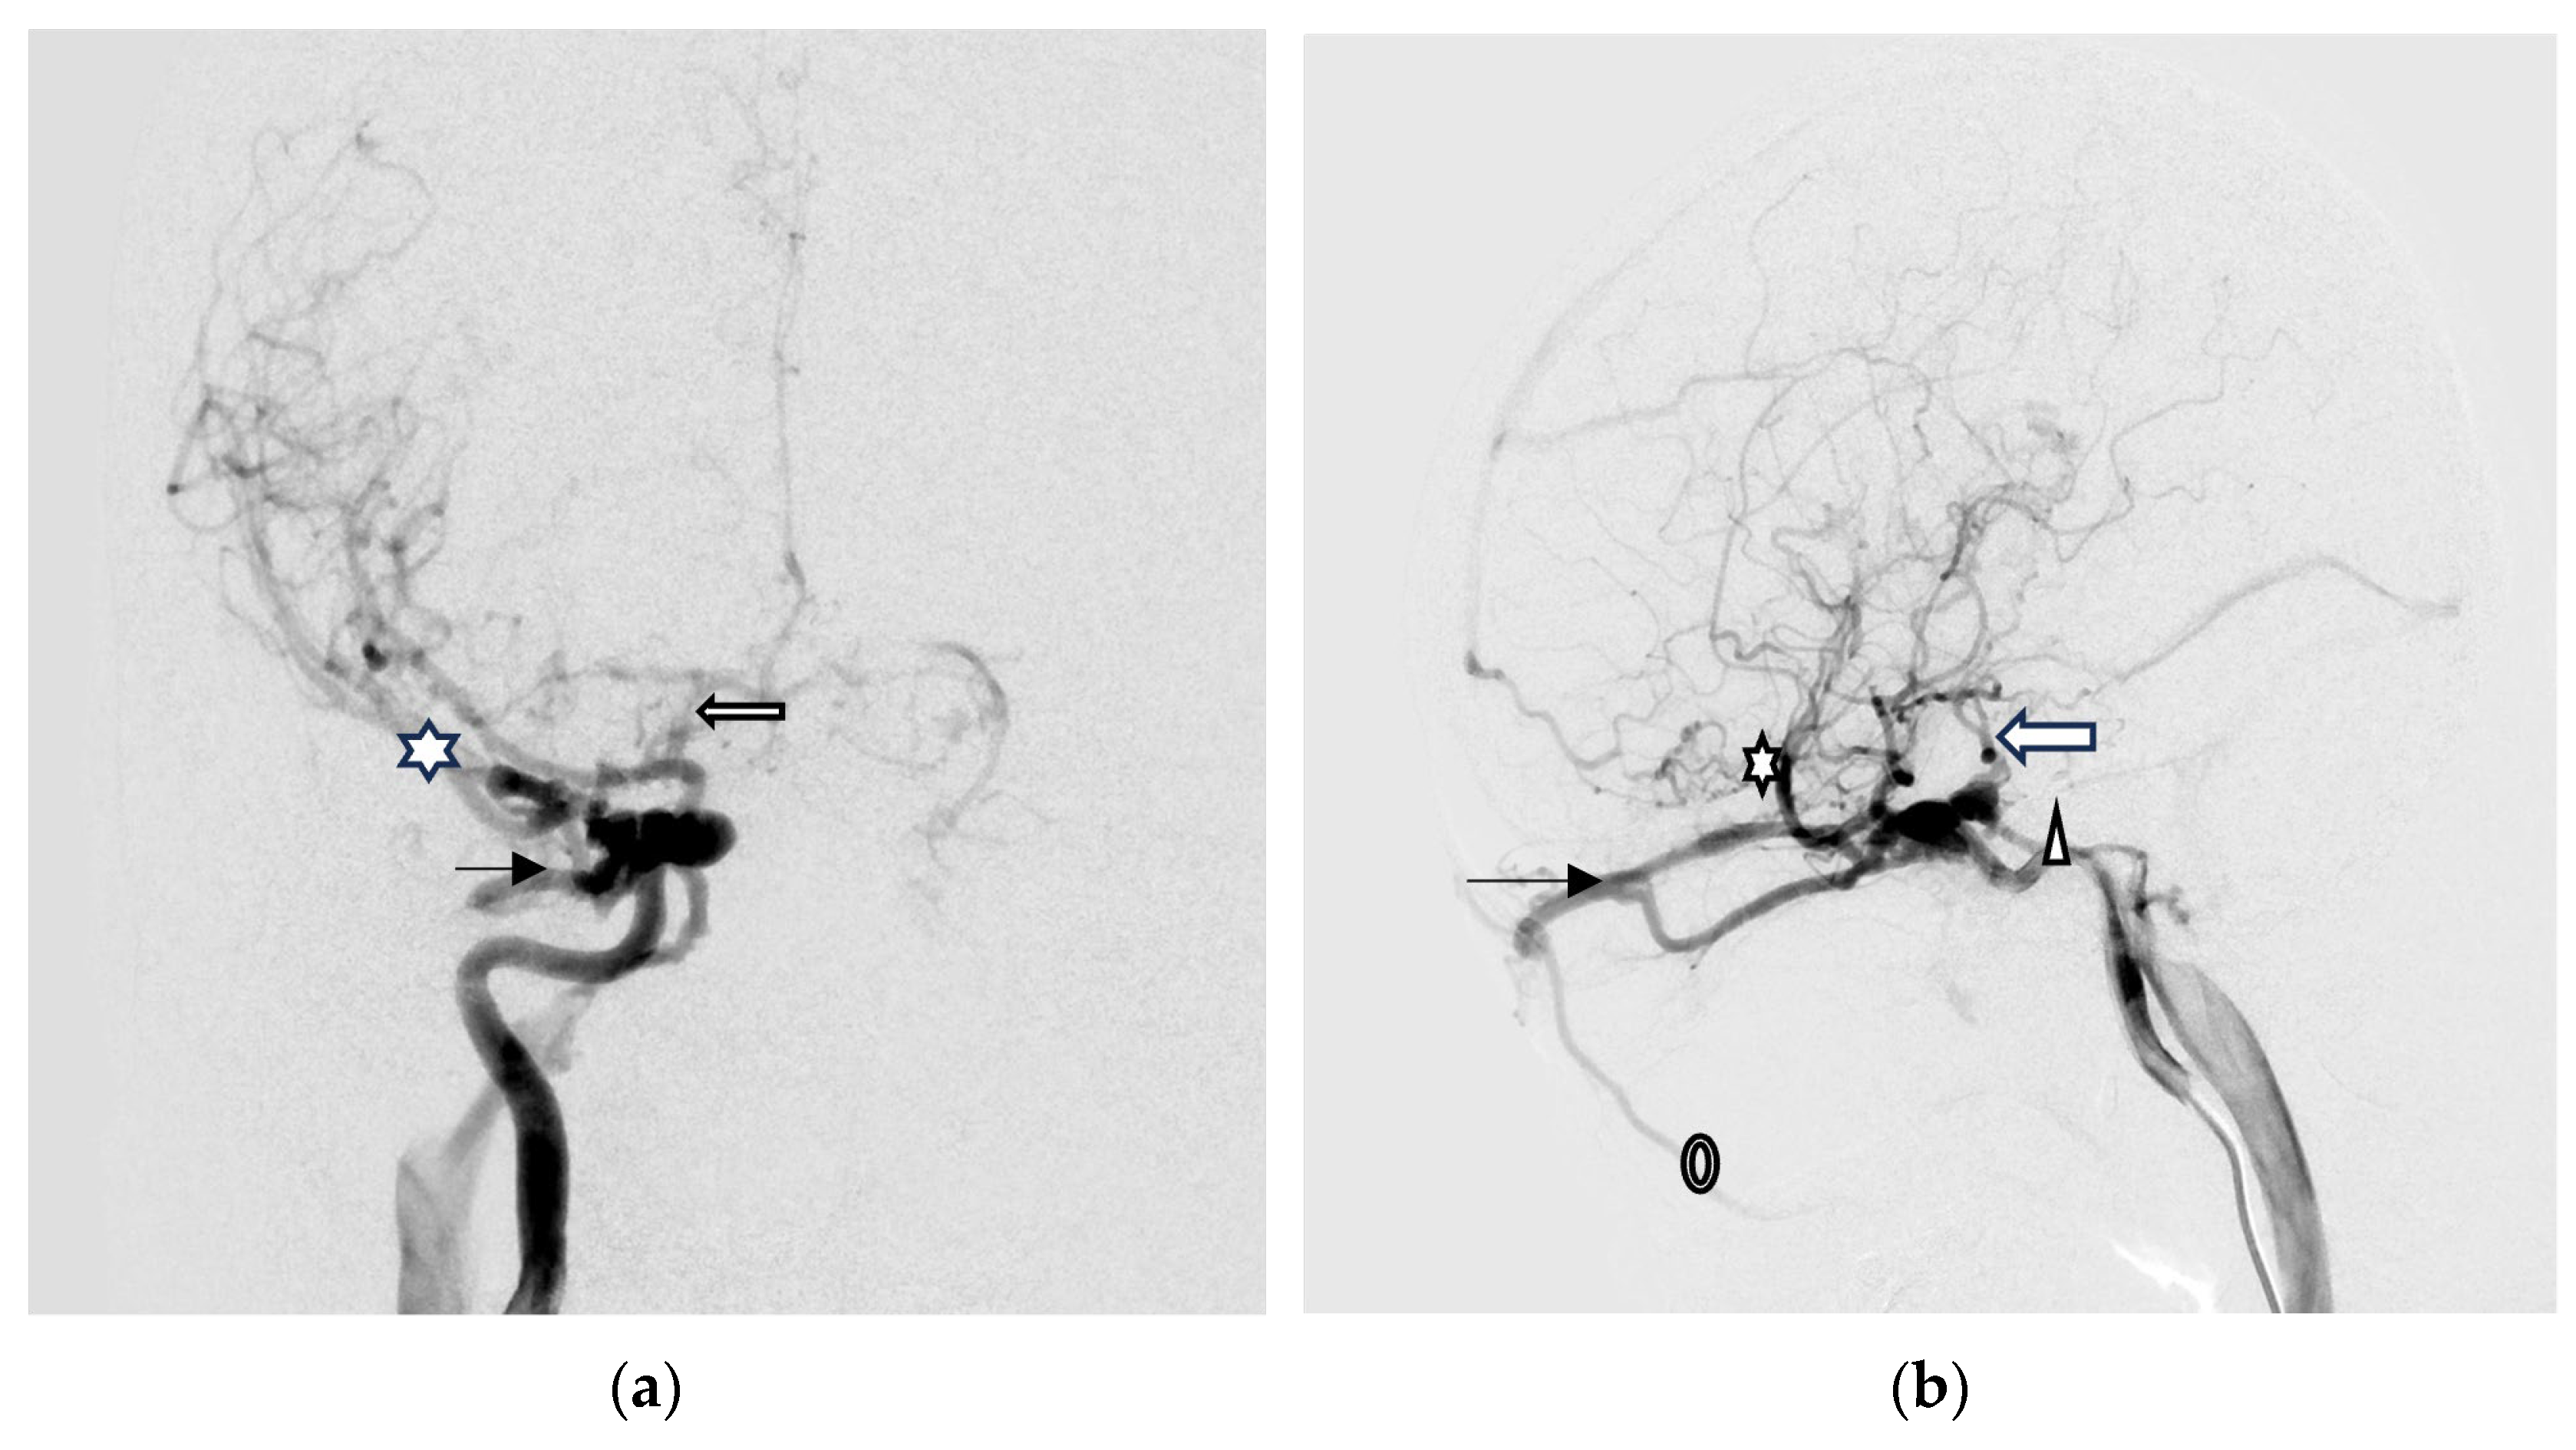

Digital subtraction angiography (DSA) was performed to confirm a direct type high-flow CCF of the right-side ICA with reflux flow into the right SOV and inferior ophthalmic vein (IOV), the right superficial middle cerebral vein (SMCV), the right superior petrosal sinus (SPS), and the right inferior petrosal sinus (IPS). Right facial vein engorgement due to SOV/IOV drainage was also noticed in the DSA (Figure 4a,b). Therefore, the CCF was classified as Barrow type A based on the arterial angioarchitecture [2] and Thomas classification type 5 based on the venous drainage pattern classification [3].

Figure 4.

(a,b) Digital subtraction angiography (DSA) anterior–posterior view (AP) and lateral (Lat) view show a direct type high-flow CCF on the right-side ICA with reflux flow into the right superior/inferior ophthalmic vein (arrow head), the right superficial middle cerebral vein (star), the right superior petrosal sinus (arrow), and the right inferior petrosal sinus (triangular). Right facial vein engorgement due to right superior/inferior ophthalmic vein drainage was also noticed in the DSA (circle); (c,d) The Guglielmi Detachable Coils (GDCs) were deployed into the CCF, resulting in occlusion of the anterior drainage part of CCF (arrow head). There were still two fistulous points in the back part of the CCF that showed severe arteriovenous shunts: one at the right sphenoparietal sinus drainage into the right superficial middle cerebral vein (star), and another at the right superior petrosal sinus (arrow). This caused severe cortical vein reflux.

A total of 28 Guglielmi Detachable Coils (GDCs) were deployed into the CCF, resulting in occlusion of the anterior drainage part (SOV/IOV) of CCF. However, there were still two fistulous points in the posterior part of the CCF showing severe arteriovenous shunts. The first was located at the right sphenoparietal sinus, draining into the right SMCV. The second was at the right SPS, which caused severe cortical vein reflux (CVR) (Figure 4c,d).